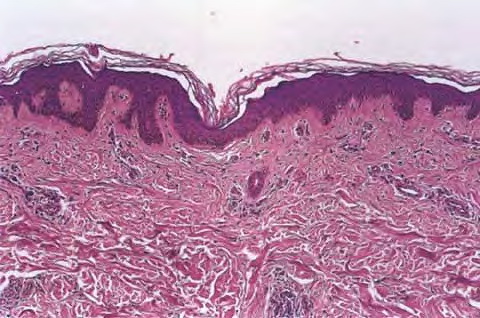

Adult mast cell disease (telangiectasia macularis eruptive perstans) =داء الخلايا البدينة عند البالغين